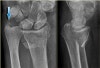

X-ray : 원위 요골 골절(Die-punch fracture)

X-ray : 원위 요골 골절(Chauffeur's fracture)